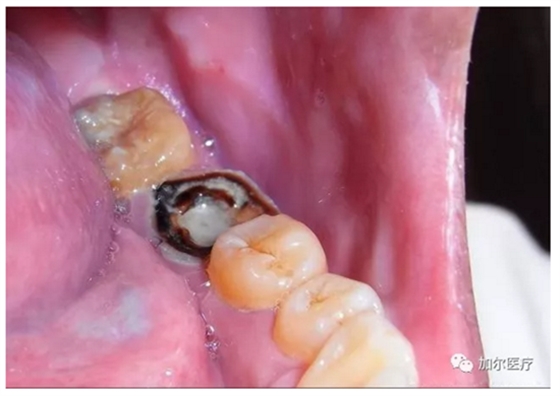

判斷牙齦上是否起膿包!

1、很遺憾地告訴你,一旦長膿包說明牙髓失去活力,甚至病變牙髓沉積在根尖部位刺激根尖周圍組織,瘺管受感染起炎癥后膿液流出,穿透牙槽骨起膿包,這種病髓就得抽出,清洗消毒髓腔以及根尖部位,并且還得封消炎藥。

2、其實說的就是根管治療,只不過多了清理根尖部位,還有牙齦膿包位置的消炎殺菌,有些患者深度蛀牙引起牙痛,明明可以早點做根管治療,拖到病髓壞死發(fā)生根尖周炎,這時候再來治療還得加錢治根尖炎,結(jié)果反而更糟還要花更多錢!